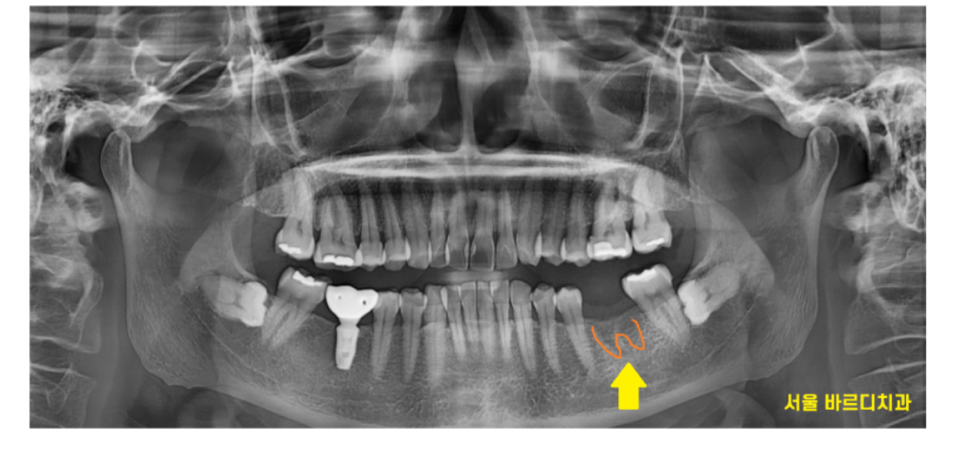

231219

발치 자국은 이런 치아 뿌리가 있었던 흔적을 뜻합니다.

시간이 지나면서 뼈가 아물기 때문에

이런 흔적들은 사라지기 마련이에요~

저런 모양이 있으면

아! 발치하신지 얼마 안됐구나!

추측할 수가 있습니다.